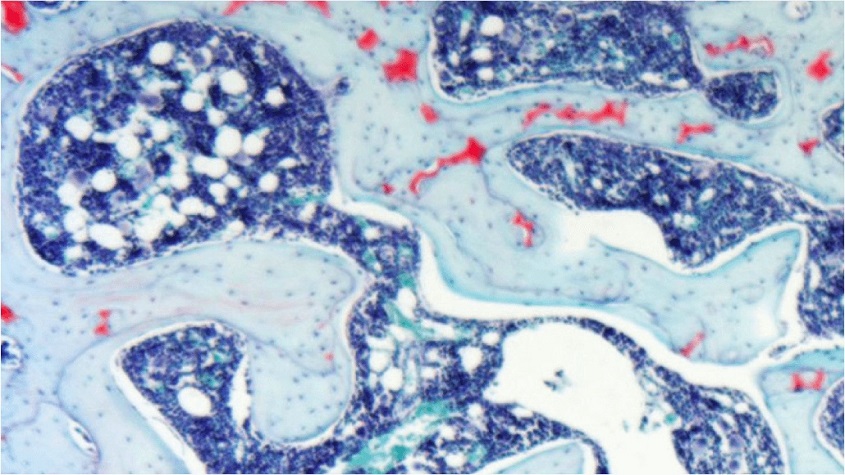

NGF is elevated in chronic pain, and inhibitors are efficacious in reducing pain in conditions such as osteoarthritis, back pain and cancer pain. However, anti-NGF antibodies (e.g. tanezumab, fulranumab) have side effects in some patients, such as rapid progression of osteoarthritis, resulting in early joint replacement. In pre-clinical models of osteoarthritis, LEVI-04 provides analgesia equivalent to that achieved with anti-NGF antibody treatment, but without rapid progression of osteoarthritis. LEVI-04 treatment restores neurotrophin homeostasis by providing stable binding proteins for the excess neurotrophins present in chronic pain states. Unlike anti-NGF antibodies that ablate NGF signalling, LEVI-04 reduces NGF activity to provide analgesia while maintaining the neurotrophin function required for cartilage and bone repair.